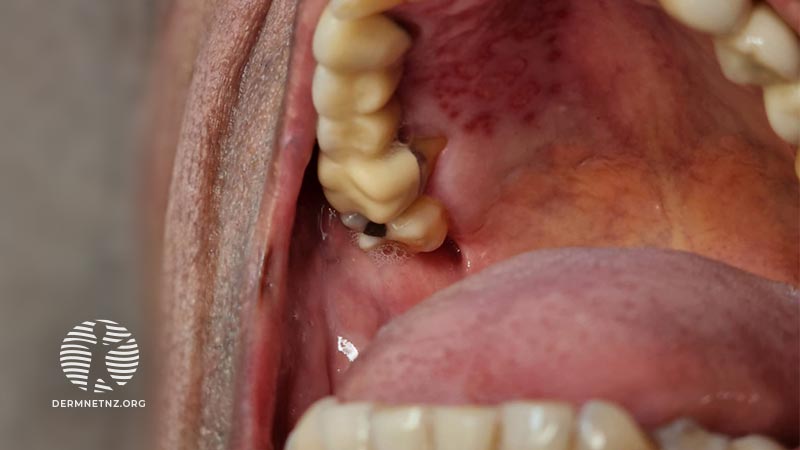

Oral ulcers and new skin blisters

Read moreArrow right small right